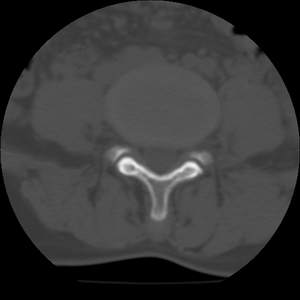

标题: CT21469:腰椎局限性呈高密度,什么原因? [打印本页]

标题: CT21469:腰椎局限性呈高密度,什么原因?

34y,做腰椎间盘扫描发现的,战友们讨论一下原因!

腰椎前缘密度较均匀增高,边缘清晰;考虑腰椎致密性骨炎可能。

考虑骨岛。患者增生硬化不明显,男34岁,腰椎非致密性骨炎好发部位、性别。

支持致密性骨炎,腰椎前缘也是致密性骨炎好发位置.

考虑腰椎致密性骨炎,其实腰椎前上角是也是致密性同炎的好发部位,只是没能引起同志们的注意。

dxy此病例程教授会诊过了,考虑骨岛。